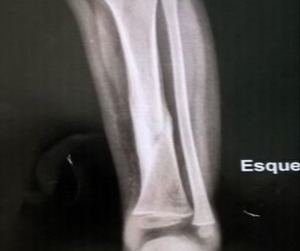

Osso

Metabolismo Ósseo

Osteogênese Imperfeita

Caso de osteogenese